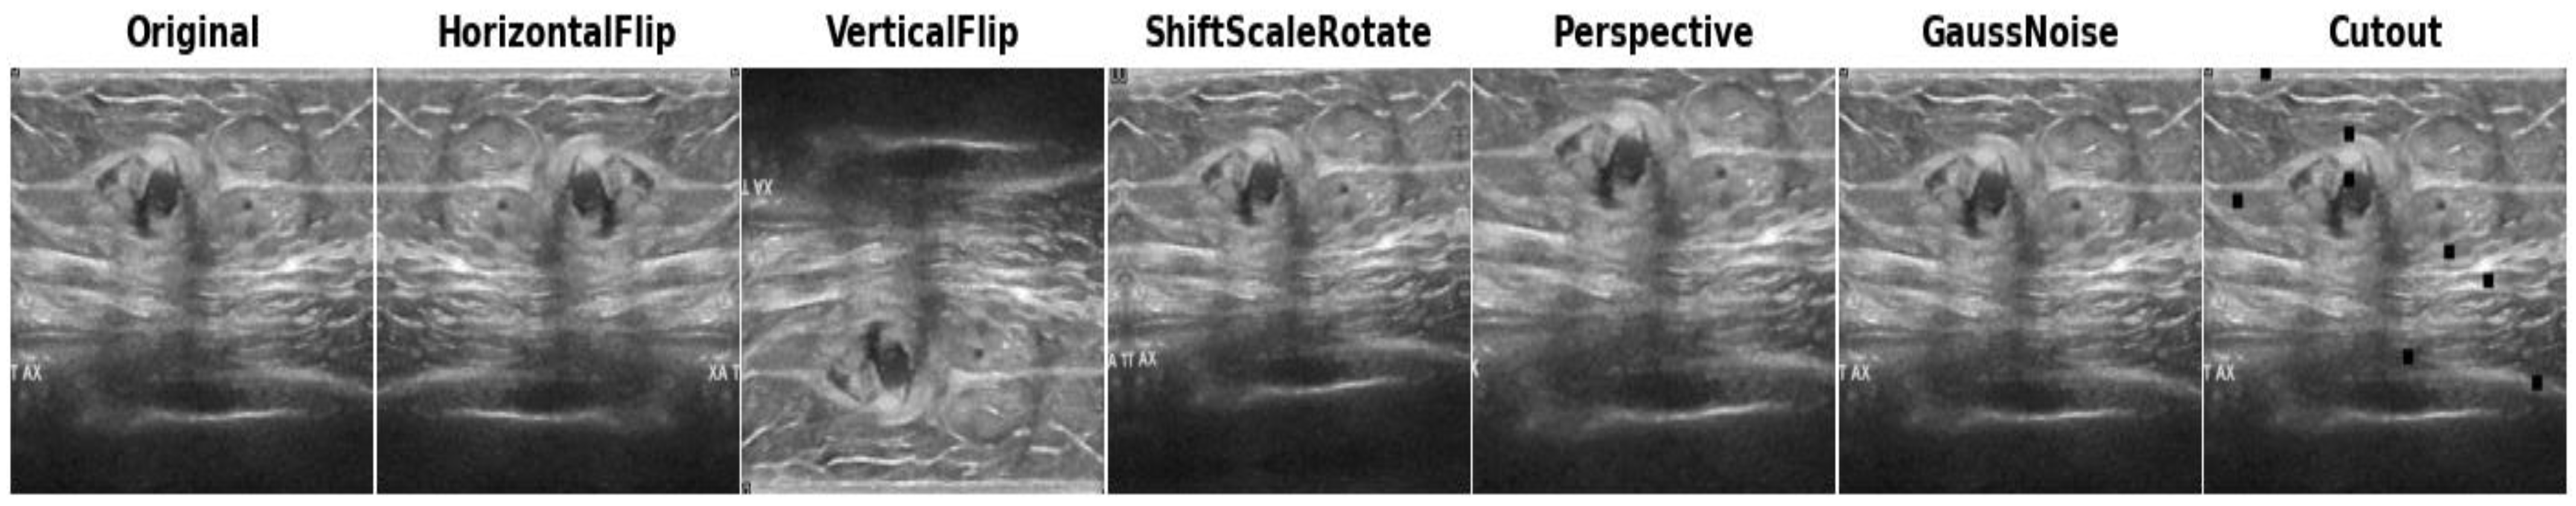

Data augmentation is a collection of techniques employed to generate additional data samples from an existing dataset [40]. The primary objective is to enrich the diversity and size of the dataset, thereby enabling ML/DL models to better learn from the available data. These techniques involve applying various transformations to the original images, such as random cropping, horizontal or vertical flipping, adding noise, blurring, random shifting, scaling, etc. During our training process, in addition to standardizing and cropping images, we integrated several data augmentation methods to augment the dataset and enhance the robustness of our models.

Before applying data augmentation, we partitioned the entire classification dataset into training and test datasets. The total dataset collected from all the sources comprised 3186 images for the classification of breast cancer in two categories: malignant and benign. Initially, the dataset was split into 80% (training data) and 20% (test data), resulting in 2548 images for training, with the remaining 638 images reserved for testing the models. Subsequently, we applied the following augmentation techniques exclusively to the training set (2548 images), while the test images were kept in reserve and not subjected to any processing techniques. Conventional augmentation such as horizontal flipping, vertical flipping, random shifts, scaling and rotations, perspective changes, and Gaussian noise addition have been applied to the real training images. These augmentation strategies were carefully selected to improve the model training and enhance the models’ ability to handle the diverse distortions often present in clinical settings. To provide a concise overview of the augmentation techniques employed, they have been organized in Table 1, while visual representations of the applied augmentation techniques can be found in Figure 3.